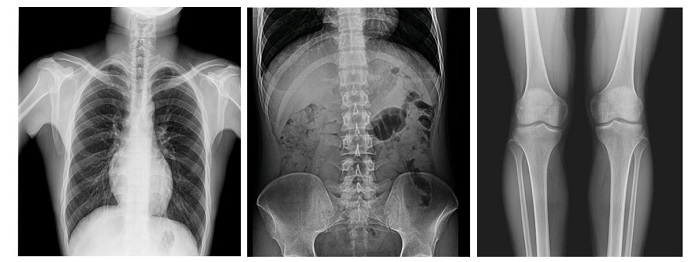

全能型動態(tài)平板,卓越圖像

配備新一代動態(tài)平板探測器,17×17英寸大幅面成像,能對患者的胸部腹部等部位實現(xiàn)大范圍全覆蓋,透視檢查無需對患者重新定位便可觀察到足夠大的人體器官組織,避免漏診誤診;最高30幀/s采集幀速,影像更加流暢,便于使醫(yī)生觀察細微病變,從而提高診斷準確率。